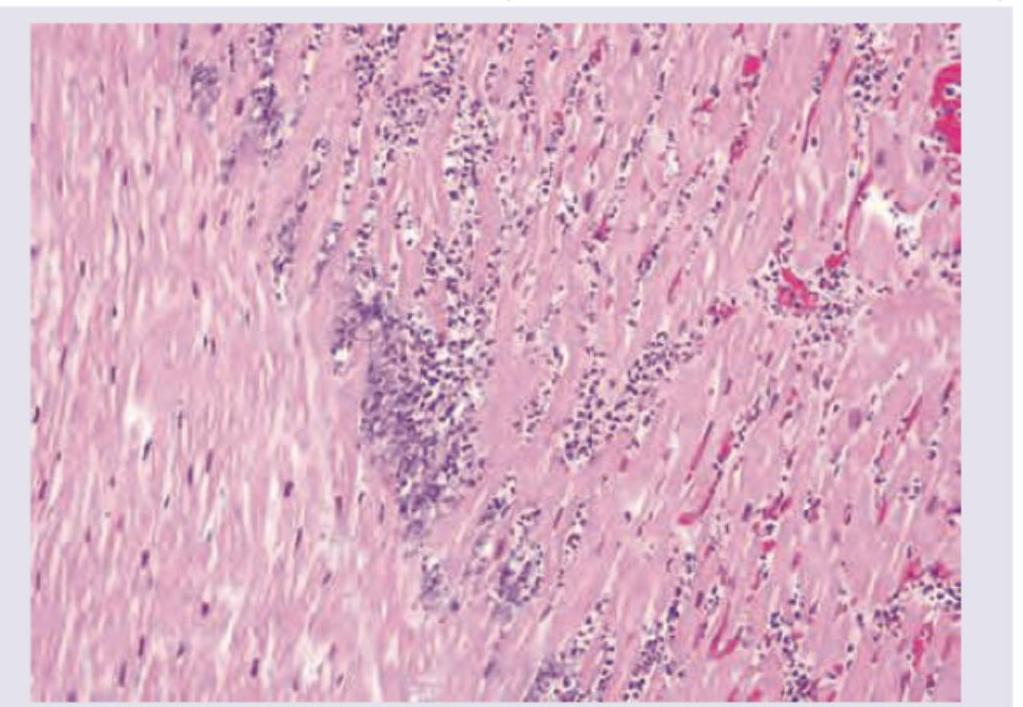

An athlete collapsed and expired while playing school basketball. Histology of the cardiac specimen is most likely to indicate which of the following conditions?

Explanation: ***Hypertrophic cardiomyopathy (HCM)*** - The image shows **myocardial disarray and hypertrophy**, characterized by haphazardly arranged and abnormally branched cardiac muscle cells with large, irregular nuclei, which is a classic histologic finding in HCM [1]. - HCM is the most common cause of **sudden cardiac death in young athletes**, often during exertion, due to ventricular arrhythmias arising from the disarrayed myocardium [1]. *Dilated cardiomyopathy (DCM)* - Histology for DCM typically shows **myocyte atrophy**, thinning of the ventricular walls, and interstitial fibrosis, not the marked disarray and hypertrophy seen here [3]. - DCM leads to **progressive cardiac enlargement and systolic dysfunction**, and while it can cause sudden death, it is less common in athletes than HCM [4]. *Restrictive cardiomyopathy (RCM)* - RCM is characterized by **stiff, non-compliant ventricles** with impaired diastolic filling, often due to conditions like amyloidosis or sarcoidosis, showing interstitial infiltration or fibrosis. - The image does not show evidence of significant **interstitial infiltration or severe fibrosis** characteristic of RCM; instead, it highlights myocyte pathology. *Arrhythmogenic right ventricular dysplasia (ARVD)* - ARVD is characterized by the **replacement of right ventricular myocardium with fibrofatty tissue**, which would be evident histologically as fat and fibrous infiltration [2]. - While ARVD can cause sudden death in athletes, the displayed image primarily shows **myocyte hypertrophy and disarray**, not extensive fibrofatty replacement [2]. **References:** [1] Kumar V, Abbas AK, et al.. Robbins and Cotran Pathologic Basis of Disease. 9th ed. The Heart, pp. 577-578. [2] Kumar V, Abbas AK, et al.. Robbins and Cotran Pathologic Basis of Disease. 9th ed. The Heart, pp. 576-577. [3] Kumar V, Abbas AK, et al.. Robbins and Cotran Pathologic Basis of Disease. 9th ed. The Heart, p. 576. [4] Kumar V, Abbas AK, et al.. Robbins and Cotran Pathologic Basis of Disease. 9th ed. The Heart, pp. 559-560.